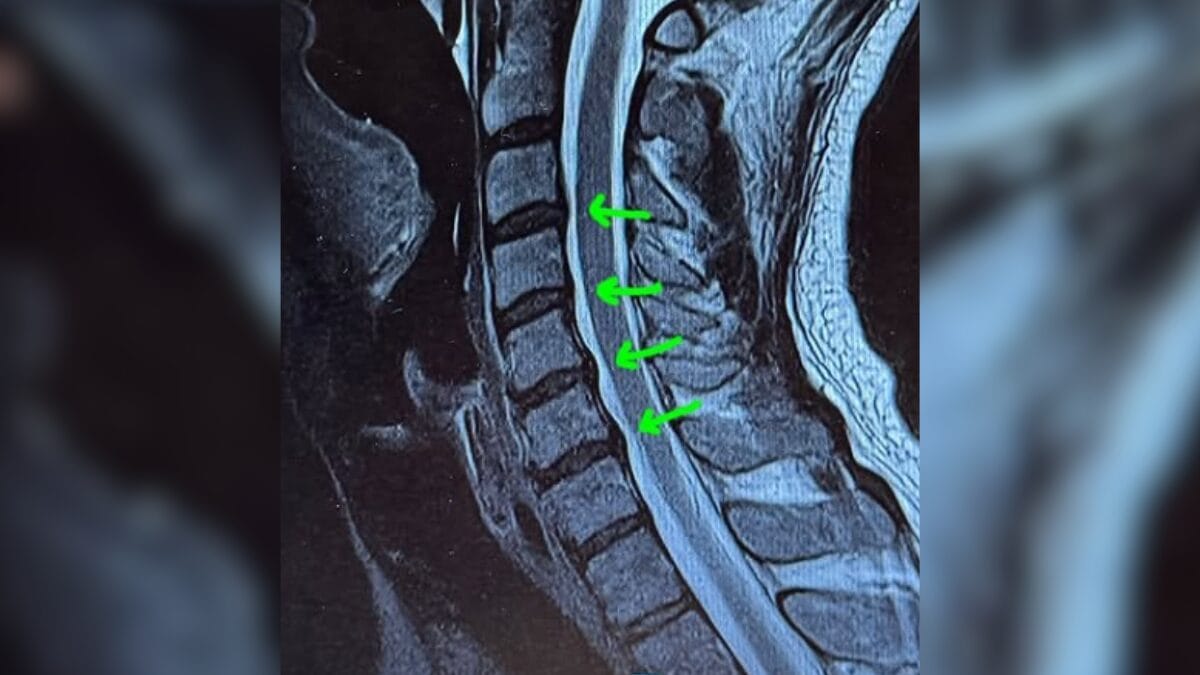

Cantor mostrou exames feitos na coluna (Foto: Redes sociais, Reprodução)

Tiago Iorc tem hérnia de disco (Foto: Redes sociais, Reprodução)

O cantor explicou que o problema vem de muitos anos de má-postura, “basicamente, por eu ficar com a cabeça baixa e o pescoço curvado por muito tempo”. Ele afirmou que teve uma crise parecida há quatro anos, ocasião em que a cirurgia já havia sido sugerida, mas que ele conseguiu contornar com tratamentos como fisioterapia, pilates e osteopatia.